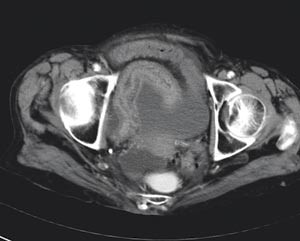

Tre timer etter innleggelsen og 19 timer etter symptomdebut ble pasienten laparotomert. Man fant hemoragiske forandringer på tynntarmsserosa i en lengde på 50 cm av distale ileum ned mot ileocøkalovergangen. Oralt for disse forandringene var det en adheransestreng som forsårsaket strangulasjonen. Etter at strengen ble delt og tynntarmsmesenteriet brettet ut, fikk man god oversikt over de makroskopiske forandringene (fig 4). Det var ingen tegn til tarmnekrose. Man observerte det affiserte tynntarmssegmentet i 15 minutter. Tarmsegmentet virket da vitalt og velsirkulert, og tarmreseksjon ble ikke funnet nødvendig. Undersøkelse i abdomen for øvrig avdekket ingen annen patologi, bortsett fra små divertikler i sigmoideum. Det postoperative forløpet var ukomplisert. Pasienten ble utskrevet til sitt eget hjem 10. postoperative dag i god allmenntilstand.